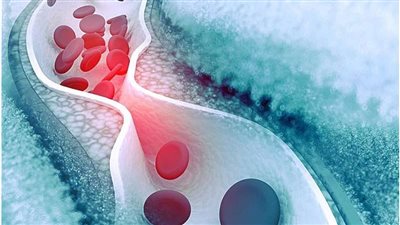

- أو كنتيجة لتجلط الدم في الوريد البابي، فقد تؤدي الجلطات الدموية إلى انسداد تدفق الدم في الوريد البابي أو في الأوردة الكبدية، مما يزيد من الضغط داخل الجهاز البابي الكبدي.

انخفاض مستويات خلايا الدم